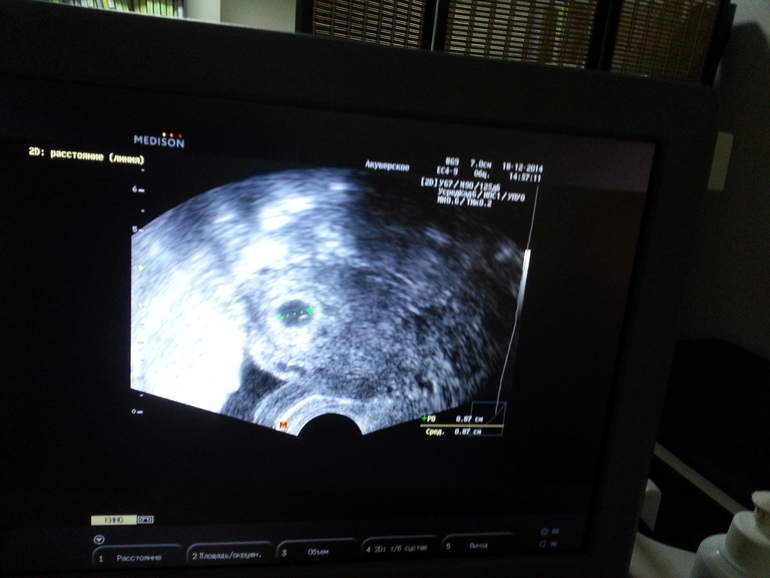

Снимок не дали, но я монитор сфоткала, сейчас выложу посмотрите я не могу разглядеть может у вас получится.

7мм на 14 ДПП это отлично! Растет примерно по 1мм в сутки)))